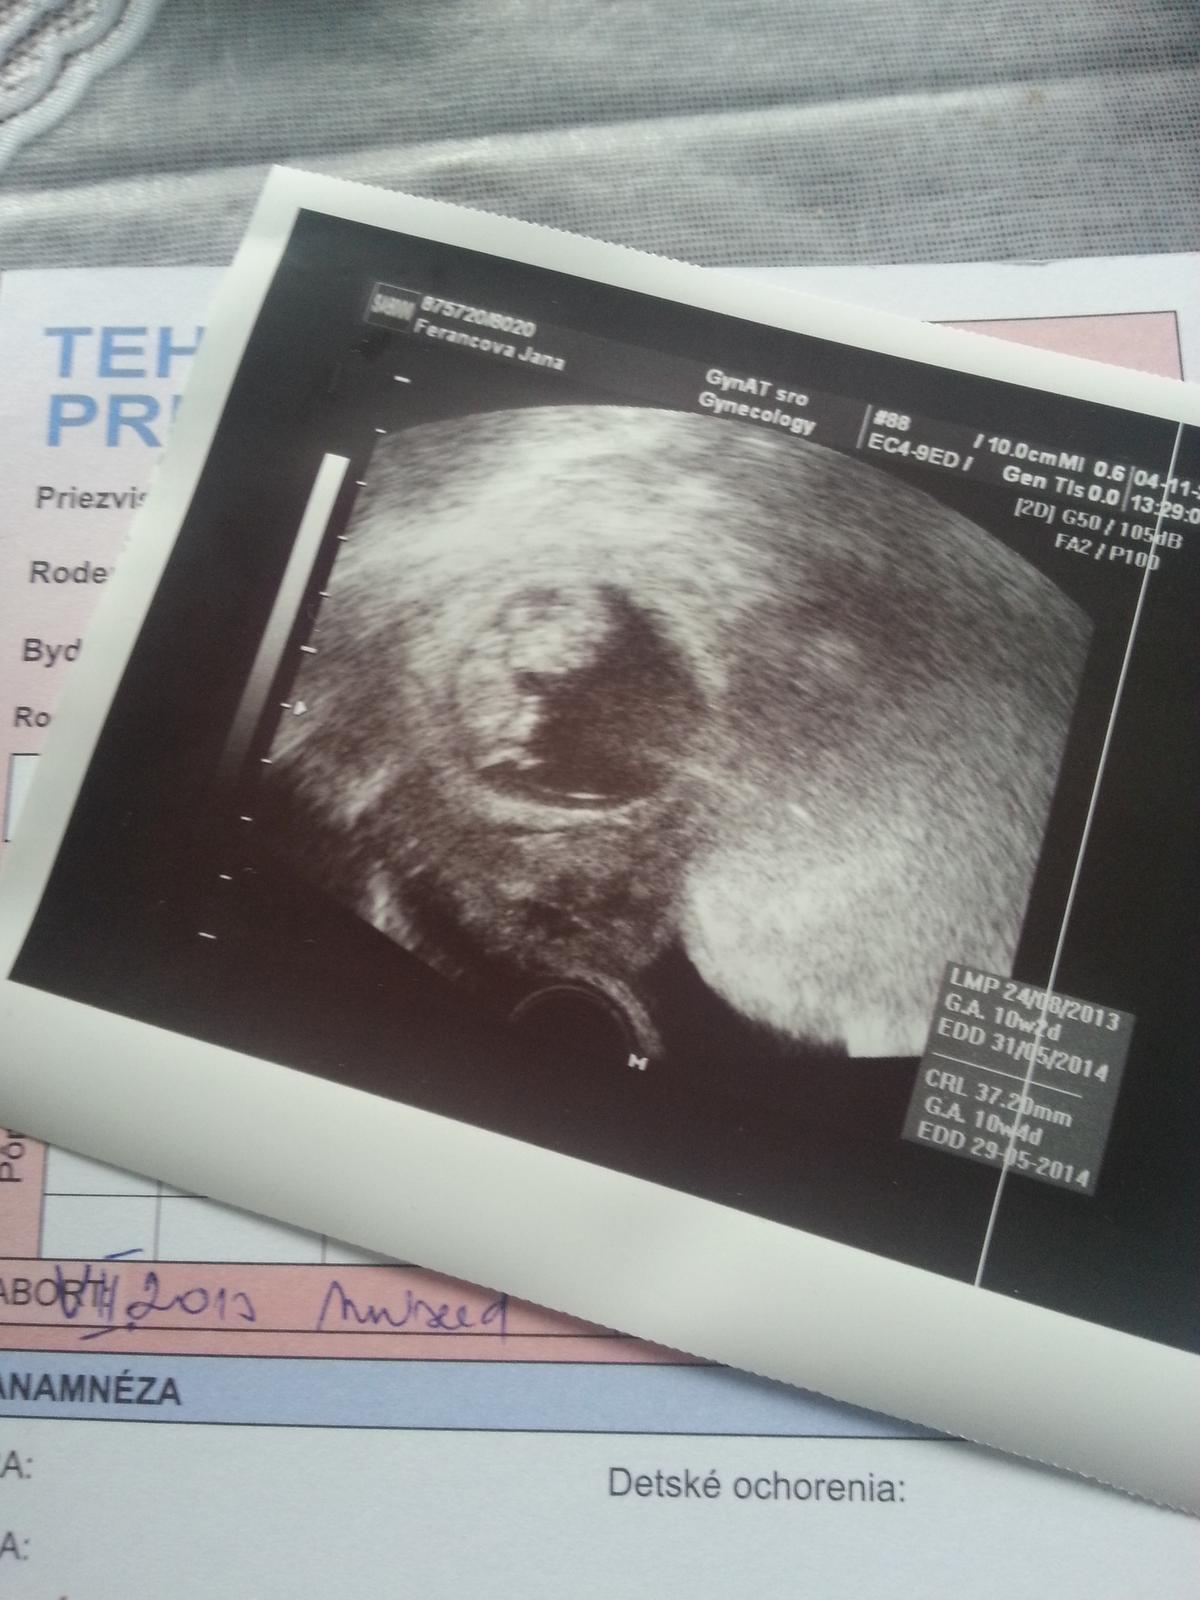

Babulky ahojte.Tak ja koncim I.trimester,este tyzden uzivania Utrogestanu,snad tie nastavajuce dva prebehnu bez komplikacii.Prikladam foto,zoznamte sa s nasim drobcekom 😉 Prva foto je na potvrdenie tehu a tato druha z prvej poradne minuly tyzden,srdiecko bilo ako zvon.Zuzi bude aj tvojmu neboj sa!

To tvoje bábätko na obrázku je také krásne, malé ňuňu, posielam mu božtek na noštek, nech je zdravučké a silné. Dúfam, že ťa poslúcha 🙂